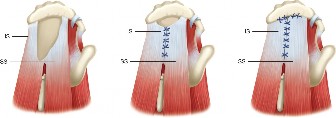

The correct answer is (A). Massive and immobile tears can be either U-shaped or longitudinal. These can sometimes be repaired using an anterior or posterior

interval slide technique. In an anterior interval slide technique, there is some anterior portion of the supraspinatus still attached to the greater tuberosity laterally and rotator interval anteriorly. The greater tuberosity attachment can be incised and the rotator interval attachment can be detached by incising the coracohumeral ligament. In a posterior interval slide technique, there is some posterior portion of the supraspinatus still attached to the infraspinatus. This can be detached by incising the interval between the supraspinatus and infraspinatus (Answer B). These interval slide techniques decrease the tension and improve lateral mobilization, allowing the supraspinatus to be more easily repaired to the greater tuberosity. The posterior leaf of the tear is then brought together with the anterior leaf through marginal convergence, leaving you with a small crescent-shaped tear that can be repaired to the greater tuberosity (see Fig. 2–16).

Figure 2–16_Massive, immobile rotator cuff tear and repair using anterior interval slide followed by marginal convergence. SS, supraspinatus; IS/TM, infraspinatus/teres minor; RI, rotator interval; CHL, coracohumeral ligament; Sub, subscapularis. (Redrawn from Burkhart SS, Lo IKY. Arthroscopic rotator cuff repair. J _Am Acad Orthop Surg. 2006;14(6):333–346.)

Crescent-shaped tears are not retracted much medially, can be mobilized laterally relatively easily, and thus can be relatively easily repaired to humeral bone (see Fig. 2–13).

Figure 2–13_Crescent-shaped rotator cuff tear and repair. SS, supraspinatus; IS, infraspinatus. (Redrawn from Burkhart SS, Lo IKY. Arthroscopic rotator cuff repair. _J Am Acad Orthop Surg. 2006;14(6):333–346.)

U-shaped tears can be repaired using marginal convergence (Answer E). U-

shaped tears have an apex that extends further medially, usually to the edge of the glenoid in the sagittal plane, and this part cannot be mobilized all the way to the greater tuberosity. Because of this lack of mobility, these tears have to be repaired using marginal convergence, which is essentially zipping up the U from the apex toward the greater tuberosity using side to side sutures to bring together the anterior and posterior leaves of the U-shaped tear. In performing this marginal convergence, you essentially are converting a U-shaped tear into a crescent-shaped tear that can be relatively easily mobilized to the greater tuberosity, allowing it to be repaired (see Fig. 2–14).

Figure 2–14_U-shaped rotator cuff tear and repair using marginal convergence. SS, supraspinatus; IS, infraspinatus. (Redrawn from Burkhart SS, Lo IKY. Arthroscopic rotator cuff repair. _J Am Acad Orthop Surg. 2006;14(6):333–346.)

Finally, an L-shaped tear resembles a tear that can be thought of as partially a crescent-shaped tear and partially a U-shaped tear. One leg of the L is the more mobile, less retracted, crescent-shaped tear which transitions into the other leg of the L, a less mobile, more retracted part of the tear which mechanically and visually resembles a U-shaped tear. The retracted U-shaped part, like a normal U-shaped tear, must be repaired using marginal convergence. Then the remaining crescent-shaped part, like a normal crescent-shaped tear, can be mobilized laterally and repaired to bone (see Fig. 2–15).

Figure 2–15_L-shaped rotator cuff tear and repair using marginal convergence. SS, supraspinatus; IS, infraspinatus; RI, rotator interval; CHL, coracohumeral ligament; Sub, subscapularis. (Redrawn from Burkhart SS, Lo IKY. Arthroscopic rotator cuff repair. _J Am Acad Orthop Surg. 2006;14(6):333–346.)